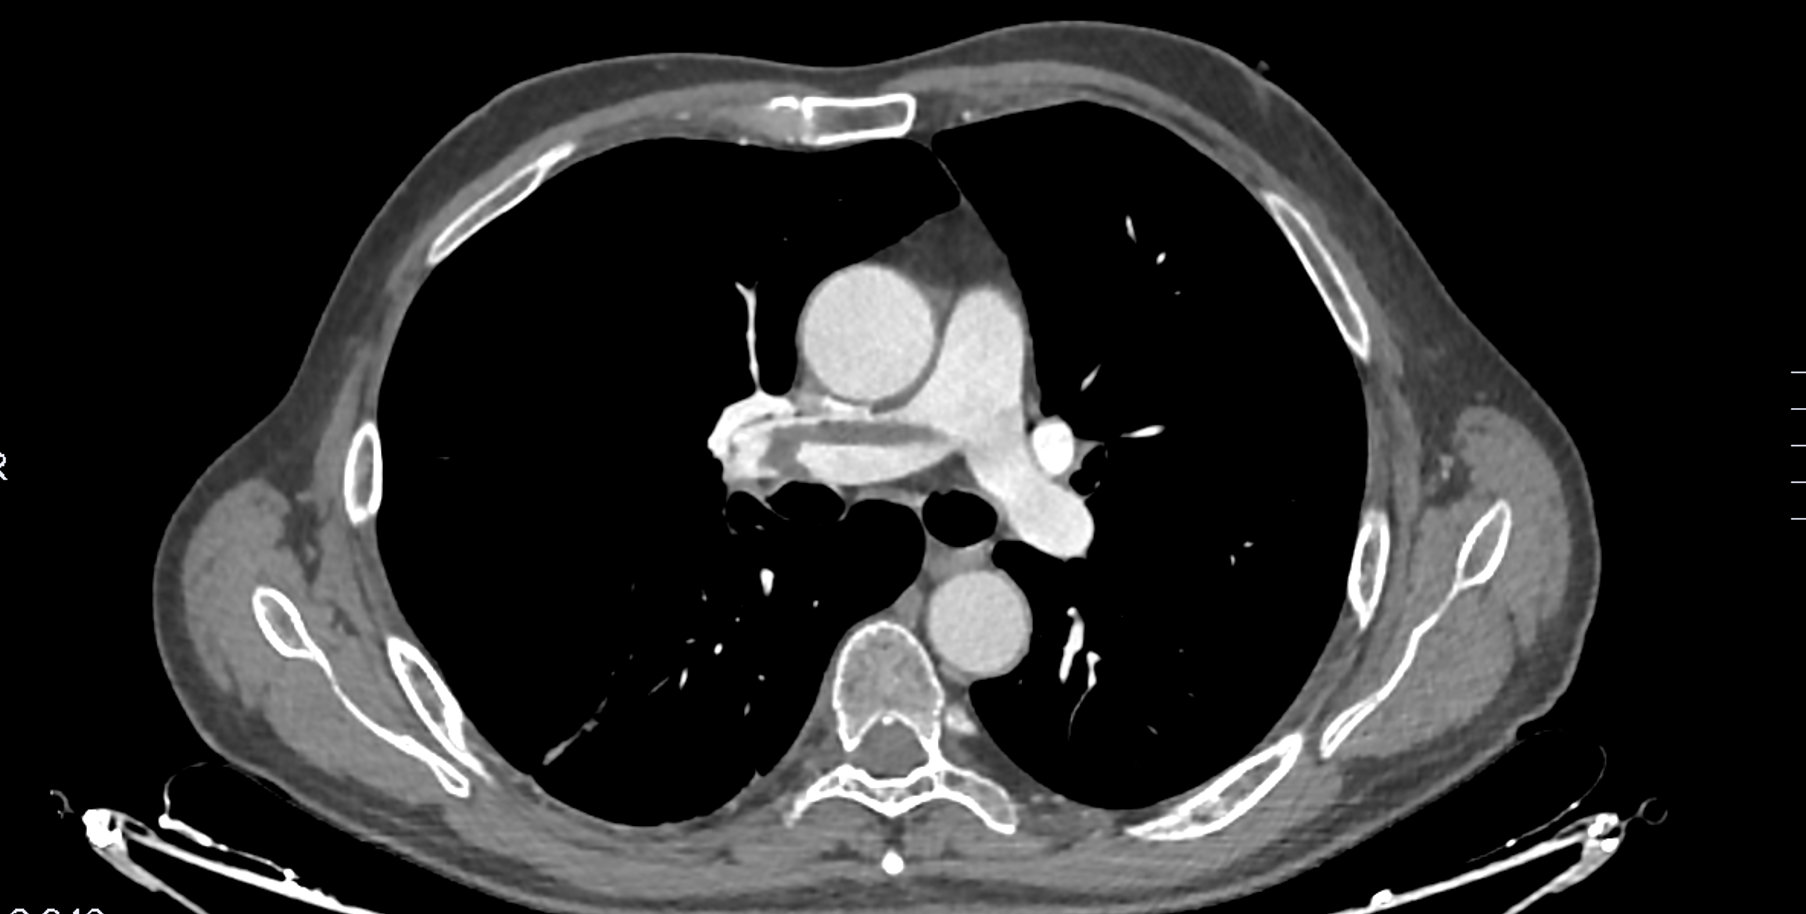

Angio-TC torácico con contraste i.v.